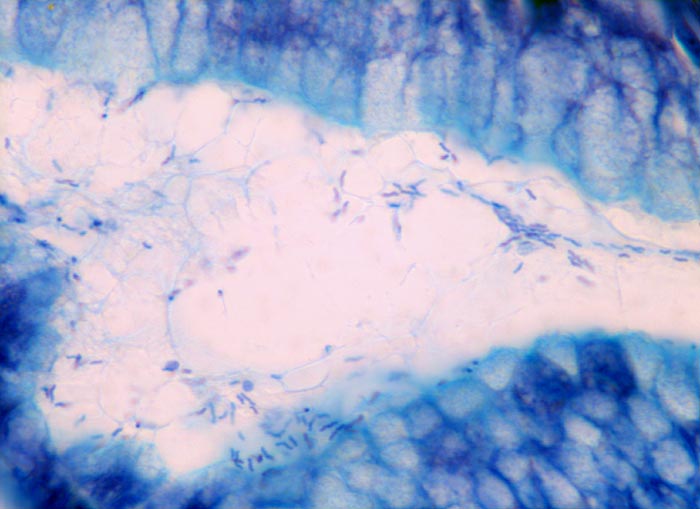

PathoPic ID 3330 - Helikobakter pylori

Helikobakter pylori

Entzündung infektiös

Magenantrum

Oesophagus, Magen

Im Schleim auf der Mukosaoberfläche finden sich zahlreiche schlanke, leicht gekrümmte Bakterien.

Chronische aktive Gastritis

Histologie

400